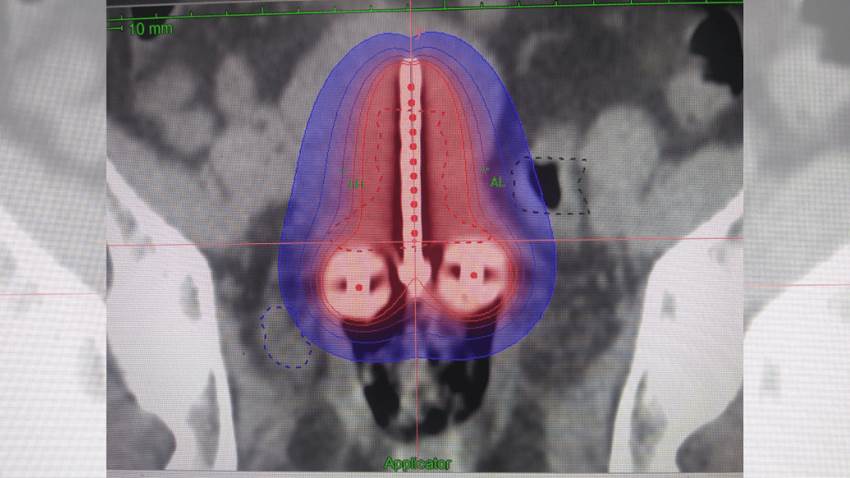

Prueba de VPH y la citología duplican posibilidad de detectar el cáncer cervical a tiempo, según estudio

Este estudio indica y confirma lo publicado recientemente por los estándares de detección de EE. UU., se trata de un estudio que indica que la combina...